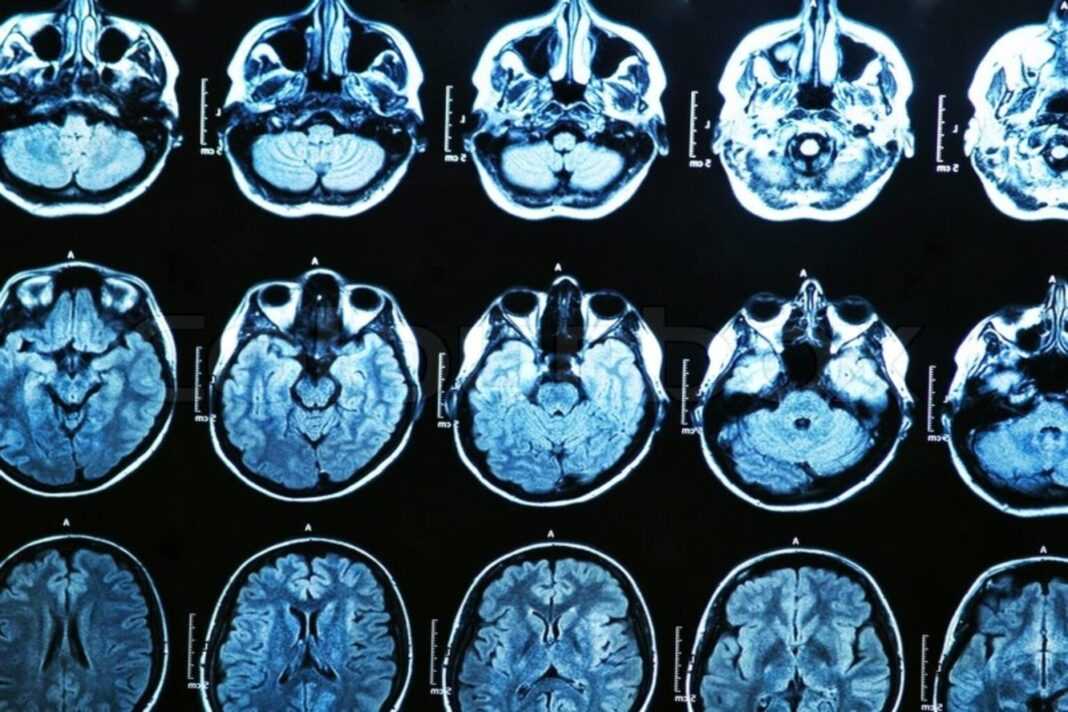

Οι ερευνητές συνέλεξαν δεδομένα για την κόπωση χαρακτηριστικών και την καταπόνηση από 43 υγιείς άνδρες και γυναίκες ηλικίας 20 έως 63 ετών. Η κατάσταση κόπωσης μετρήθηκε κατά τη διάρκεια σαρώσεων fMRI ενώ οι συμμετέχοντες εκτέλεσαν μια γνωστικά απαιτητική εργασία. Η μελέτη διεξήχθη στο Rocco Ortenzio Neuroimaging Center στο Kessler Foundation, μια εξειδικευμένη εγκατάσταση αφιερωμένη αποκλειστικά στην έρευνα αποκατάστασης. Διαπίστωσαν ότι τα ηλικιωμένα άτομα ανέφεραν λιγότερη κούραση.

Ο Δρ Wylie, διευθυντής του Κέντρου Ortenzio, σχολίασε: “Τα δεδομένα νευροαπεικόνισης μας δείχνουν ότι ο ρόλος των μεσαίων μετωπιαίων περιοχών του εγκεφάλου αλλάζει με την ηλικία. Τα νεότερα άτομα μπορεί να χρησιμοποιήσουν αυτές τις περιοχές για να καταπολεμήσουν την κόπωση, αλλά αυτό δεν συμβαίνει με τα μεγαλύτερα άτομα Επιπλέον, αυτά τα αποτελέσματα υποδηλώνουν ότι οι γυναίκες δείχνουν μεγαλύτερη ανθεκτικότητα όταν αντιμετωπίζουν ένα κουραστικό έργο”.